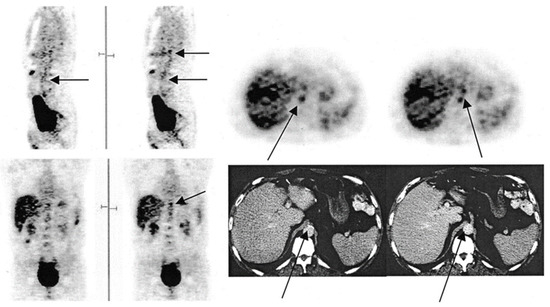

Conventional imaging modalities, including ultrasonography, CT, and MRI angiography, are widely used clinically to visualize large symptomatic plaques but are limited in their ability to assess the early stages of atherosclerosis [71,72]. In contrast, molecular imaging offers a tantalizing opportunity to examine the pathological hallmarks of atherosclerotic disease at the microscopic level [73]. As discussed previously, FDG demonstrates remarkable sensitivity and specificity for inflammatory lesions (Figure 1). Further, FDG was postulated to be effective in the identification of the inflammatory precursor lesions that precede calcific atherosclerotic disease. Yun et al. first examined vascular FDG uptake in 137 patients who underwent FDG-PET scanning [23]. They observed that over half of the subjects demonstrated vascular FDG uptake, with a greater prevalence among older individuals. Further studies demonstrated that vascular inflammation as assessed by FDG was associated with proinflammatory molecular and cellular markers of atherosclerosis [24,25,26].

Figure 1.

FDG-PET images illustrating the foci of FDG uptake along the aorta. In the sagittal view, the arrow in the left image indicates the abdominal aorta, while the top arrow on the right points to the budding superior mesenteric artery. In the transverse view, the bottom and top arrows indicate the abdominal aorta and budding superior mesenteric artery, respectively. In the coronal view, the arrow points to the budding mesenteric artery. In the CT image, the left arrow points to calcification along the abdominal aorta, while the right indicates to the budding superior mesenteric artery (from Yun et al. [23] with permission).